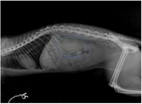

Při následném RTG vyšetření v boční poloze je v superprojekci patrná normální zdravá ledvina (zelenožluté šrafování) a zřejmě patologicky zvětšená druhá ledvina (modré šrafování). Na druhém snímku v dorsoventrální poloze byl nalezen velký kulovitý útvar na pravé straně dutiny břišní v místě, kde by se u zdravé kočky měla nacházet pravá ledvina (na obrázku označen modře).